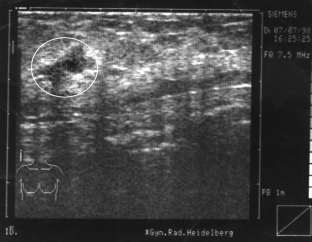

Am Montag kam eine Freundin zu mir, sagen wir, sie heißt Marga (40 Jahre), und war ziemlich aufgelöst. Sie sagte, sie habe einen großen und schmerzhaften Knoten in der linken Brust. Sie war vor ein paar Tagen deshalb bei einer Untersuchung und der Prof. sagte, sie müsse ihn dringend, und zwar so schnell wie möglich, rausnehmen lassen, denn die Gefahr sei groß, daß er streut. Sie selbst hat auch das Gefühl, daß der Knoten bösartig ist. Sie hat das Ultraschallbild und zeigt es mir. Man sieht einen fast runden großen, dunklen Fleck mit vier grauen unscharfen Ausbuchtungen. Marga nennt sie „die vier Ecken“.

Vorher:

Nachher: